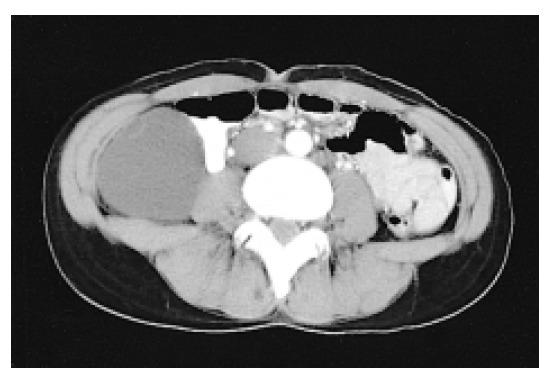

Primary mucinous cystic cystadenomas of the retroperitoneum are very rarely encountered, and there have been only about 30 cases reported in the literature. The histogenesis of primary mucinous cystadenomas is unclear. Most authors suggested that it develops through mucinous metaplasia in a pre-existing mesothelium-lined cyst. Complete surgical excision is the only treatment and it is required for the final diagnosis and cure. We present here a case report of a 38-year-old Korean woman with primary retroperitoneal cystadenoma. It was a thin-walled, multilocular cyst with a dominant loculus that measured 10.0 x 7.5 x 5.5 cm3 in size, and to the best of our knowledge, this is the first such case to be reported in in Korea.

原发性腹膜后黏液性囊腺瘤非常罕见,文献中仅报道过约30例。原发性黏液性囊腺瘤的组织发生尚不清楚。大多数作者认为它是由先前存在的间皮衬里囊肿中的黏液化生发展而来。完整的手术切除是唯一的治疗方法,也是最终诊断和治愈所必需的。我们在此报告一例38岁韩国女性原发性腹膜后囊腺瘤的病例。这是一个薄壁、多房囊肿,其中一个主腔大小为10.0×7.5×5.5 cm³,据我们所知,这是韩国首例此类病例报告。